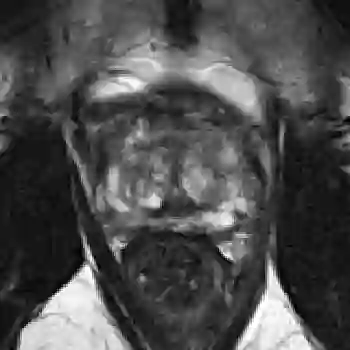

The emergence of multi-parametric magnetic resonance imaging (mpMRI) has had a profound impact on the diagnosis of prostate cancers (PCa), which is the most prevalent malignancy in males in the western world, enabling a better selection of patients for confirmation biopsy. However, analyzing these images is complex even for experts, hence opening an opportunity for computer-aided diagnosis systems to seize. This paper proposes a fully automatic system based on Deep Learning that takes a prostate mpMRI from a PCa-suspect patient and, by leveraging the Retina U-Net detection framework, locates PCa lesions, segments them, and predicts their most likely Gleason grade group (GGG). It uses 490 mpMRIs for training/validation, and 75 patients for testing from two different datasets: ProstateX and IVO (Valencia Oncology Institute Foundation). In the test set, it achieves an excellent lesion-level AUC/sensitivity/specificity for the GGG$\geq$2 significance criterion of 0.96/1.00/0.79 for the ProstateX dataset, and 0.95/1.00/0.80 for the IVO dataset. Evaluated at a patient level, the results are 0.87/1.00/0.375 in ProstateX, and 0.91/1.00/0.762 in IVO. Furthermore, on the online ProstateX grand challenge, the model obtained an AUC of 0.85 (0.87 when trained only on the ProstateX data, tying up with the original winner of the challenge). For expert comparison, IVO radiologist's PI-RADS 4 sensitivity/specificity were 0.88/0.56 at a lesion level, and 0.85/0.58 at a patient level. Additional subsystems for automatic prostate zonal segmentation and mpMRI non-rigid sequence registration were also employed to produce the final fully automated system. The code for the ProstateX-trained system has been made openly available at https://github.com/OscarPellicer/prostate_lesion_detection. We hope that this will represent a landmark for future research to use, compare and improve upon.